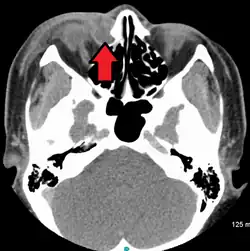

A case of dacryocystitis as seen on CT scan

Dacryocystitis is an infection of the lacrimal sac, secondary to obstruction of the nasolacrimal duct at the junction of the lacrimal sac.[1] The term derives from Greek dákryon 'tear' cysta 'sac' and -itis 'inflammation'.[2] It causes pain, redness, and swelling over the inner aspect of the lower eyelid and epiphora. When nasolacrimal duct obstruction is secondary to a congenital barrier it is referred to as dacryocystocele. It is most commonly caused by Staphylococcus aureus and Streptococcus pneumoniae.[3] The most common complication is corneal ulceration, frequently in association with S. pneumoniae.[3] The mainstays of treatment are oral antibiotics, warm compresses, and relief of nasolacrimal duct obstruction by dacryocystorhinostomy.[3]